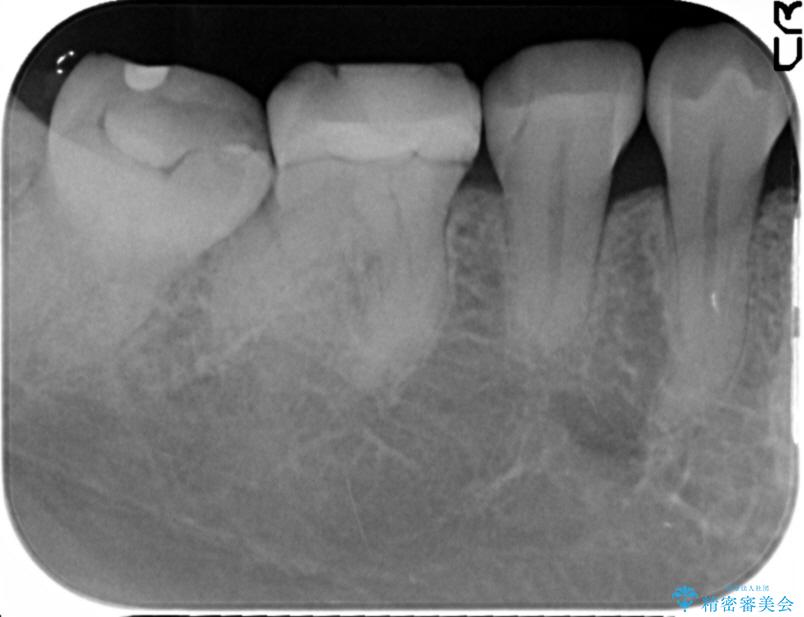

治療後について

詰め物の下に隙間がある場合、隙間に細菌が侵入し虫歯が再発してしまう可能性があります。また、詰め物が割れたり外れたりしてしまう危険性もあります。

ですのでもし隙間が見つかった場合には再度治療をすることをお勧めいたします。

治療完了した歯でも、時間の経過や力的作用によってセメントが変性したり、隙間が空くことによって詰め物の下に虫歯が発生したりすることがあります。

そうならないためにも適合の良い剛性にも優れた素材を用いた治療を求められます。特にセラミックが使用されたインレーは見た目が自然なだけでなく適合性、剛性共に高い水準を持つためリスクを減らすことができます。